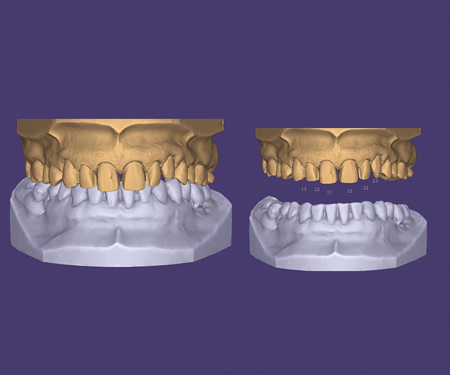

数字化修复

数字化